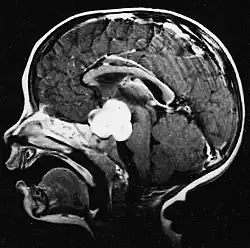

Sagittal T1-weighted MRI showing a well-circumscribed hypointense mass in the tectum (presumably a tectal plate glioma). These lesions are a distinct subset of pilocytic astrocytoma which present with hydrocephalus typically in 6 to 10 year-olds and are rarely progressive lesions. When imaging is characteristic, a biopsy is usually not performed because of the risks to adjacent structures, often shunting to relieve intracranial pressure is the only treatment required.

T1-weighted coronal MRI image postcontrast showing heterogeneous contrast enhancement within the presumed tectal plate glioma